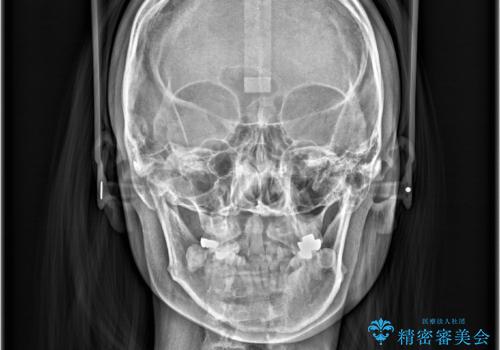

骨格的顎の変位を認めたため、顔貌に対しピッタリ上下の歯の正中を合わせることは難しいと説明し、上下左右計4本小臼歯を抜歯しワイヤー矯正治療を行いました。

右側第二小臼歯、左側第一小臼歯、下顎両側第一小臼歯を抜歯しワイヤ-矯正を行いました。